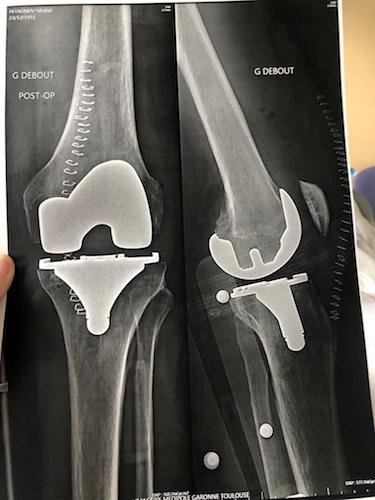

Michel s’est payé le luxe d’un séjour en clinique du 14 au 18 novembre. Il est sorti le vendredi après avoir fait une photo de face et de profil de son genou opéré.

Sur la photo de gauche, nous pouvons remarquer la jolie couture, ce qui lui donne de bonnes chances d'être embauché en CDI chez Singer sans période d'essai.

Le genou de Michel.jpeg

Le genou de Michel.jpeg (31.89 Kio) Vu 2897 fois